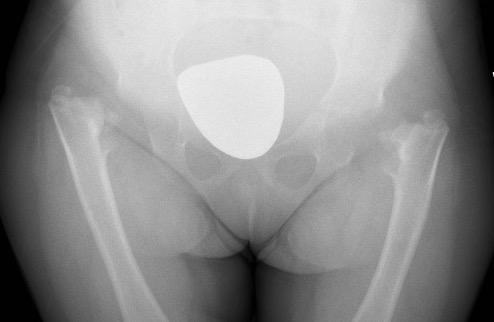

Developmental Coxa Vara

Epidemiology

Rare

Male = female

Bilateral in 1/3

Xray

| Varus femoral neck | Inverted Y | Hilgenreiner's epiphyseal angle |

Neck-shaft angle < 125°

Normal is 150° in infant |